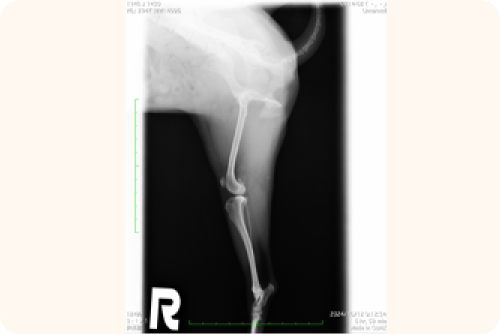

レントゲン検査

X線撮影により、以下の点を詳細に確認します。

• 膝蓋骨の位置と脱臼の方向

• 骨の変形や捻れ

• 変形性関節症の進行度

• 関節炎の有無

この検査結果は、手術の必要性や具体的な手術方法を決定する上で重要な情報となります。

骨の位置関係や、前十字靭帯損傷時に見られる特徴的な所見(ファットパットサインなど)を確認します。

視診や触診後、レントゲン検査を行い、骨がどのような位置にあるのかを詳しく調べます。また、レントゲン写真では膝の関節内にある脂肪組織の位置も確認します。この脂肪組織の位置が変わっていることで、前十字靱帯が傷んでいないかどうかの手がかりを得ることができます。